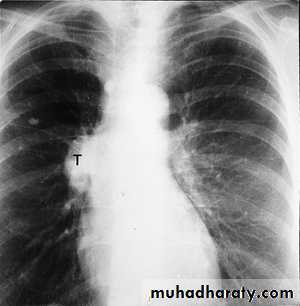

squamous cell carcinoma in which a portion of the tumor demonstrates central cavitation,

The main aims of investigations are to confirm the diagnosis, establish the histological cell type and define the extent of the disease.1- CXR: common radiological features of lung cancer:

Unilateral hilar enlargement.

Peripheral pulmonary opacity.

Lung, lobe or segmental collapse.

Pleural effusion.

Broadening of mediastinum, enlarged cardiac shadow, elevation of a hemidiaphragm.

Rib destruction.